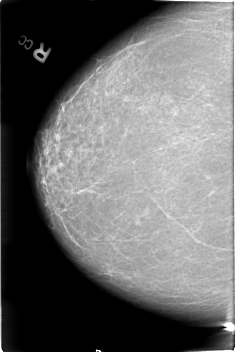

B_3018_1.RIGHT_CC

RIGHT_CC LINES 4568 PIXELS_PER_LINE 3072 BITS_PER_PIXEL 12 RESOLUTION 50 NON_OVERLAY